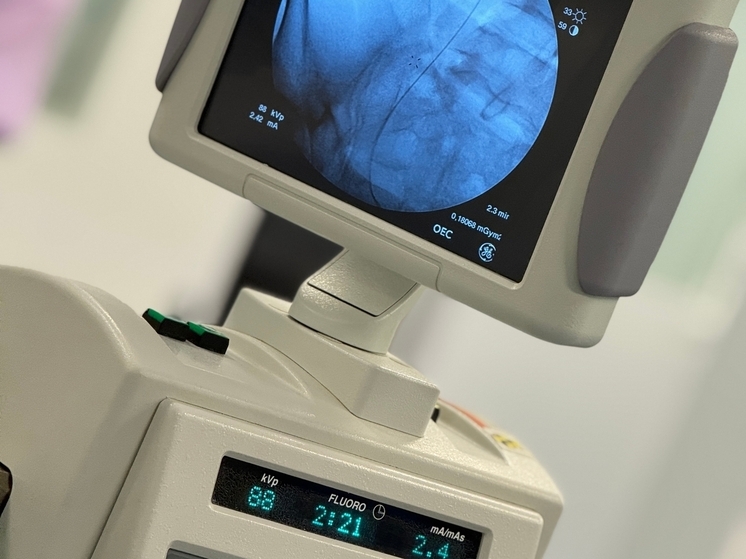

В ходе показательных операций бескровным доступом, без единого разреза, с помощью гибкого уретерореноскопа были удалены сложные конкременты. Михаил Мурушиди отметил, что важнейшим аспектом безопасности является комбинированный визуальный и рентгенологический контроль, который позволяет точно позиционировать инструмент и исключить повреждения.